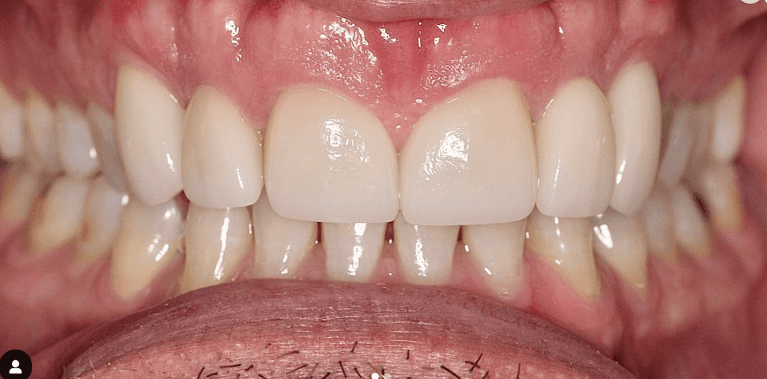

Invisalign Orthodontic treatment completed in 8 months to straighten teeth and improve esthetics.